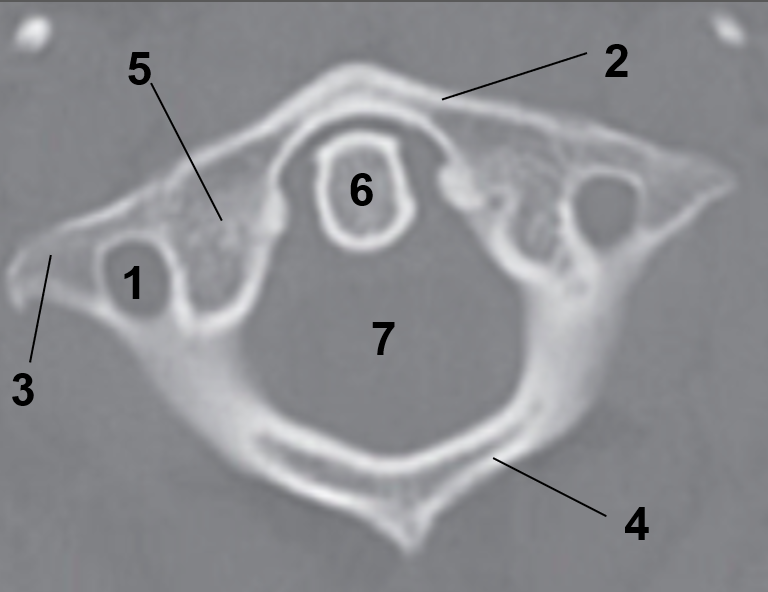

1?

Hard Palate

2?

Maxillary Bone

3?

Mandibular Rami

4?

Dens

5?

Transverse Foramen C1

6?

Spinal Cord

7?

Auricle

8?

Atlas